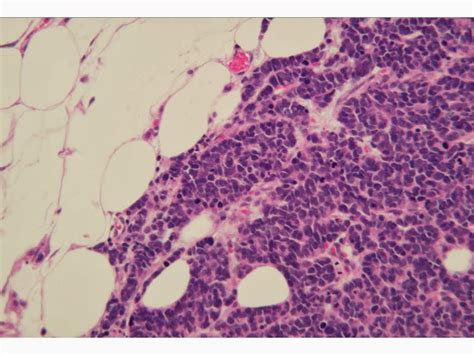

Mccs are dermally based tumors composed of small uniform round blue 31.

Merkel Cell Carcinoma | H&E, 40x Contributed by Juan A ...

Merkel cell carcinoma without a skin primary tumor cases were identified as previously described 13 as lymph node metastasis revealing the cancer, with no previous history of cutaneous merkel cell. Merkel cell carcinoma arising from the subcutaneous fat of the arm with intact skin. Merkel cell carcinoma tends to grow fast and to spread quickly to other parts of your body. Merkel cell tumors express both neuroendocrine and epithelial markers. Neuroendocrine carcinoma (merkel cell tumor?) presenting as a subcutaneous tumor.